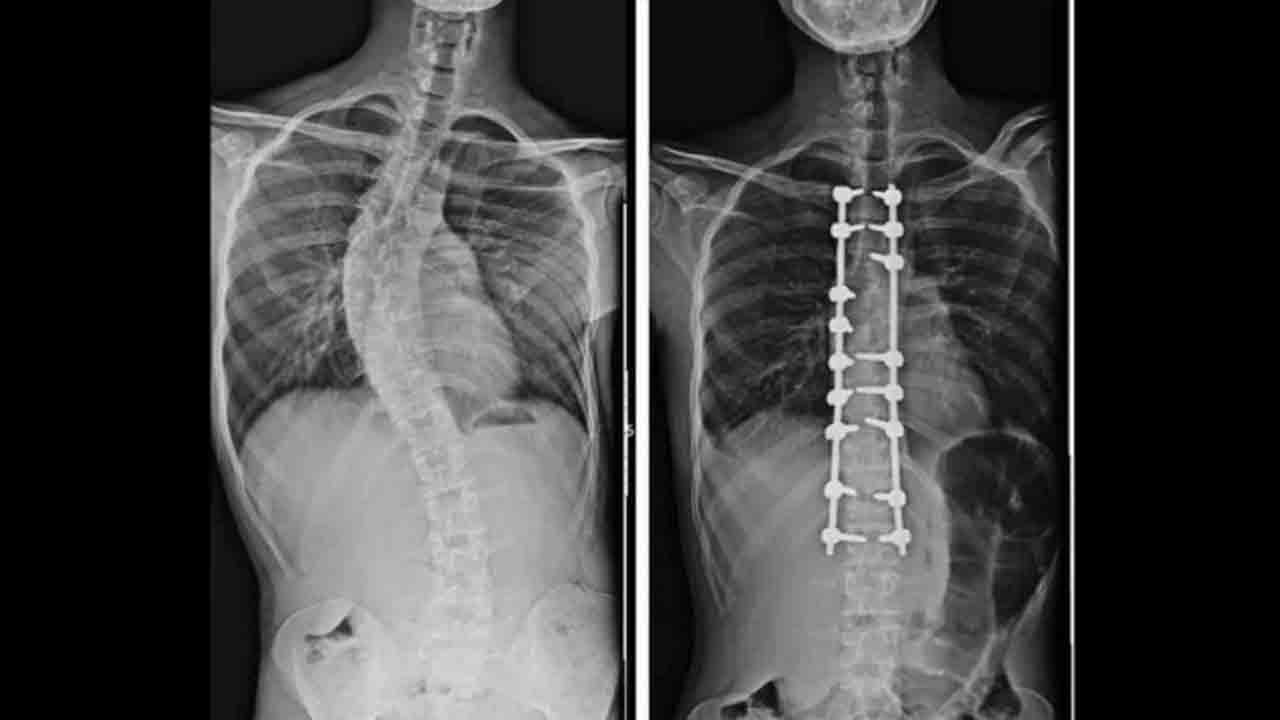

Samsun Ondokuz Mayıs Üniversitesi (OMÜ) Tıp Fakültesi’nden Doç. Dr. Hüseyin Sina Coşkun, ortopedi ve travmatolojide robot teknolojileri ile yapay zekânın hızla yaygınlaştığını ve bu sayede kişiye özel tedavi planlamasında hata payının en aza indiğini vurguladı. Doç. Dr. Coşkun, "Yapay zeka, hangi tedavi yönteminin hangi hasta için daha uygun olduğu, hangi yöntemlerin tercih edilmemesi gerektiği gibi konularda önemli katkılar sağlıyor" dedi.

OMÜ Tıp Fakültesi Ortopedi ve Travmatoloji Anabilim Dalı Öğretim Üyesi Doç. Dr. Hüseyin Sina Coşkun, ortopedi alanında kullanılan yapay zeka ve robot teknolojilerine ilişkin bilgi verdi. Özellikle çocuklarda yapılan erken müdahale ile doğru tedavinin önemini vurgulayan Doç. Dr. Coşkun, "Çocukluk çağında görülen ortopedik rahatsızlıklarda erken tanı büyük önem taşıyor. Düz tabanlık, skolyoz, kalça çıkıklığı gibi sorunlar küçük yaşlarda tespit edildiğinde erken müdahale çok önemli oluyor. Ancak günümüzün önemli bir gerçeği var; tablet ve telefon kullanımının artmasıyla birlikte duruş bozuklukları ciddi şekilde çoğaldı. Telefon ve tabletle uzun süre vakit geçiren çocuklarda hareketsizlik artıyor, bu da omurga yapısını ve genel vücut duruşunu olumsuz etkiliyor. Hareketsiz yaşam tarzına bağlı olarak pek çok ortopedik rahatsızlık daha erken yaşlarda görülmeye başlandı” diye konuştu.

Yapay zeka, hangi tedavi yönteminin hangi hasta için daha uygun olduğu, hangi yöntemlerin tercih edilmemesi gerektiği ve uygulanacak tedavinin uzun vadede nasıl sonuçlar doğurabileceğinin öngörülmesi konularında önemli katkılar sağlıyor. Bu teknolojiler sayesinde daha kişiselleştirilmiş ve doğru tedavi planları oluşturulabiliyor. Yapay zekanın ortopedideki kullanım alanı oldukça geniş. Özellikle küçük çocukların tedavisinde, omurga ve omurilikle ilgili hastalıklarda bu teknolojilerden yoğun şekilde yararlanılıyor” ifadelerini kullandı.

Küçük çocuklarda duruş bozukluğu, kamburluk ve skolyoz gibi problemlerin geçmiş yıllara göre arttığını belirten Dr. Coşkun, şöyle konuştu: "Bu tür rahatsızlıklar son derece önemli ve ne kadar erken müdahale edilirse tedavi süreci o kadar başarılı oluyor. Ortopedik hastalıklarda en önemli nokta, mümkünse hastalığın hiç ilerlememesini sağlamak. Önleyici yaklaşımlar bu nedenle büyük değer taşıyor. Ancak bir hastalık ortaya çıkmışsa da erken tanı sayesinde çok daha hızlı ve etkili bir şekilde tedavi sürecine başlanabiliyor."